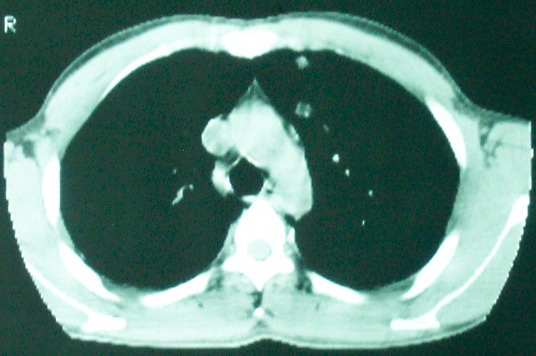

m      37y      发热   咳脓痰月余      ct肺脓肿但住院抗炎治疗后双肺内结节不知该如何解释

治疗后见左肺下野病灶较前缩小但双肺内结节影似无变化请较各位老师该如何下结论    治疗前wbc14.5 治疗后wbc 11.0

血源性肺脓肿,一般由原发感染灶引起脓毒败血症,在肺部形成小脓肿,病变变化快,容易形成肺气囊,脓气胸,主要与转移瘤鉴别,通过临床病史可分

结合病史考虑血源性肺脓肿,与转移瘤鉴别

左下肺病灶除了明显的厚壁空洞 气液平外,明显见壁结节,另两肺多发小结节,综合考虑:左下肺周围性肺癌伴肺内转移.

鳞癌肺肺转移:厚壁空洞,洞壁厚薄不均,内似有壁结节,肺脓肿临床有无提示,血像如何?病灶周围很干净,没有明显渗出,很勉强?

如果你仔细的同层面对比,你会发现所有的病灶均有比较明显的吸收、缩小。病变的形态,特别是脓肿的形态、壁的厚薄、内壁均有很大的变化,均在往好的方面发展。与临床症状、血像均符合,治疗效果比较显著,就是肺脓肿并双肺的化脓性炎症灶。